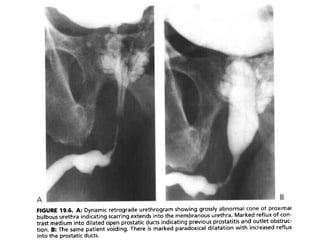

• The typical urethrographic finding in gonococcal urethral stricture is

an irregular urethral narrowing several centimeters long.

• While the bulbar urethra is the most common area of occurrence,

gonorrheal strictures may occur anywhere in the anterior urethra or

may even involve the entire anterior urethra

Gonococcal urethral stricture. Retrograde

urethrogram reveals a segment of irregular, beaded narrowing

in the distal bulbous urethra with opacification

of the left Cowper duct

• If the disease has spread proximaly to the

membranous urethra, the normal cone shape of

the proximal bulbous urethra becomes

asymmetric and narrowed, giving an elongated

appearance to the membranous urethra.

• Abnormality of the normal convex cone shape of

the proximal bulbous urethra indicates scarring

extending into the membranous urethra.

• High intraurethral pressure proximal to a stricture

not only results in dilation of the urethra, but also

can cause reflux of urine into the prostatic ducts.

• Ostia for these ducts, 30 to 40 in number, are

found in the floor of the prostatic urethra around

the verumontanum.

• This reflux may be massive and may allow

infection to enter the prostate, potentially

resulting in a prostatic abscess or formation of

multiple prostatic calculi.